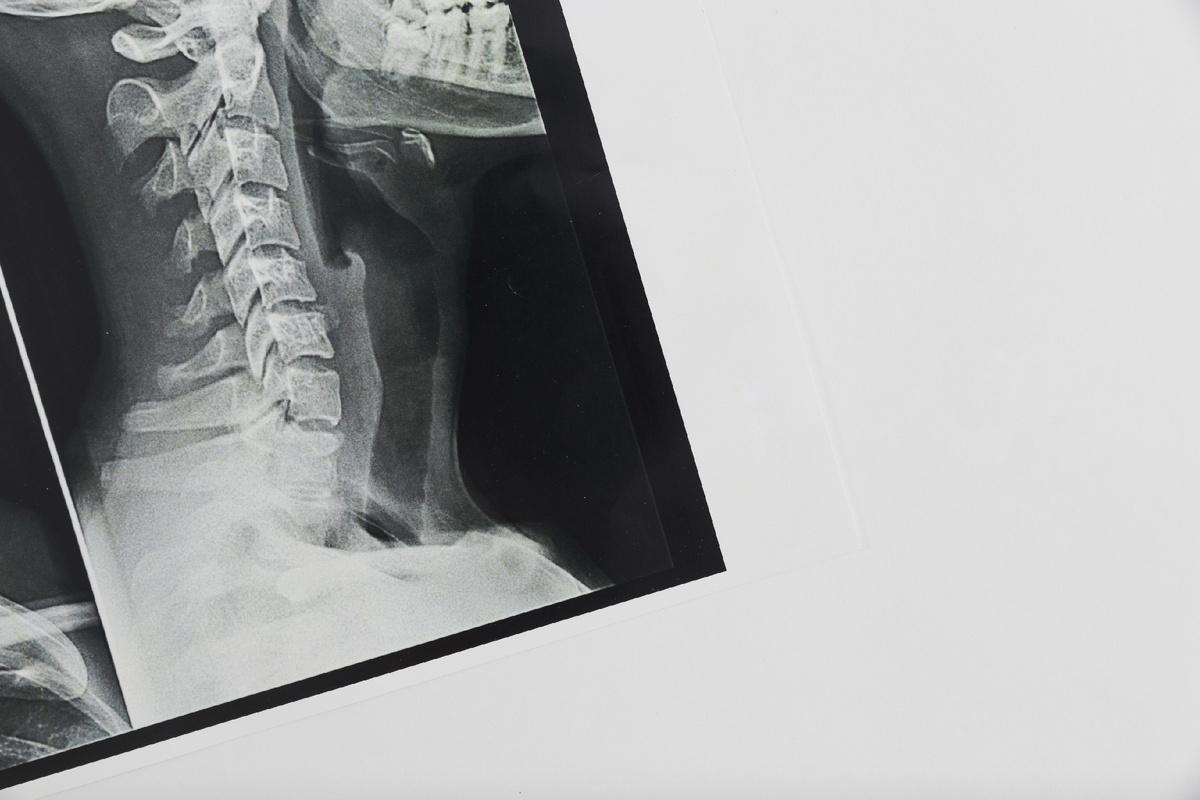

Остеопороз - это заболевание, характеризующееся снижением плотности костной ткани и увеличением риска переломов. Наиболее подвержены ему пожилые люди, особенно женщины в постменопаузе. Однако профилактика остеопороза возможна в любом возрасте, и для этого достаточно следовать нескольким простым рекомендациям: